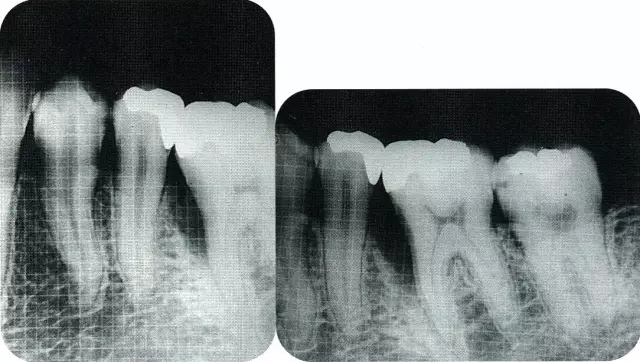

640.webp (1).jpg

▲圖7-2  術(shù)前x片。確認(rèn)存在垂直性深骨缺損。

640.webp (6).jpg

▲圖7-7  術(shù)前,術(shù)后的x片。確認(rèn)出現(xiàn)骨再生,牙槽嵴硬線。